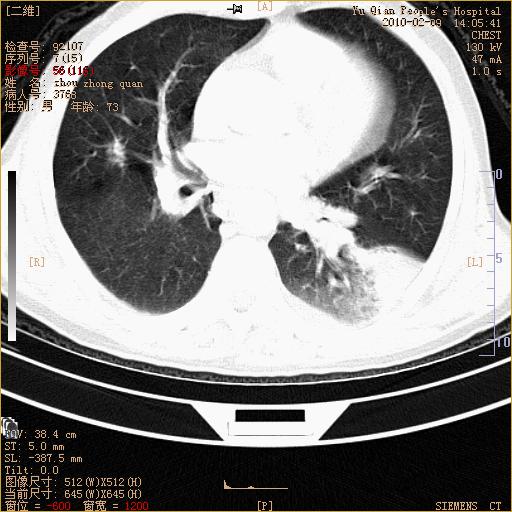

男性,73岁,咳嗽咳血数天,诊为肺ca伴左肺下叶后段阻塞性炎症、肺不张妥否?

右下肺有转移?

左下肺中央型肺癌伴结段形肺不张,左侧胸腔积液,纵隔内见部分增大淋巴结(反应性增生或转移)

左下基底干支气管明显变窄。

左肺下叶基底段支气管狭窄,左肺门增大,左肺下叶团片状病灶。中心型肺癌伴柱塞性炎症可能大,建议支气管镜检查。

左下肺中央型肺癌伴节段性肺不张,左侧胸腔积液,纵隔内见肿大淋巴结

左下基底段支气管变窄。建议进一步纤支镜检查。

1、左肺下叶后基地段肺癌伴阻塞性炎症,左下肺门淋巴结转移。2、左侧胸腔积液。